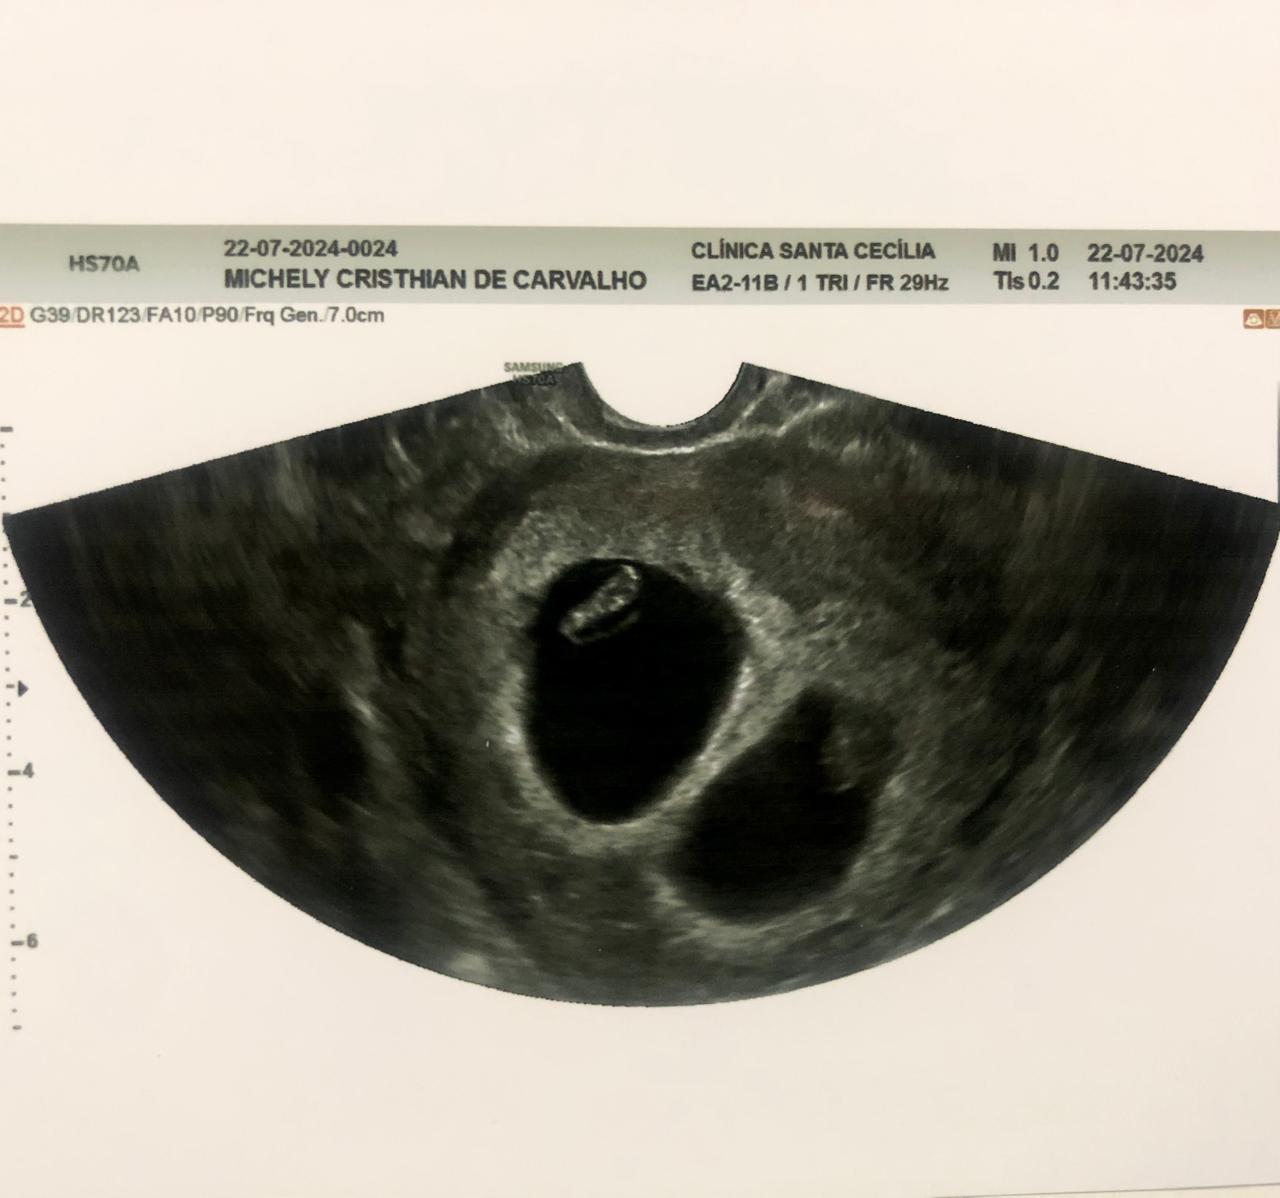

A primeira reação foi de espanto. Depois aquele impulso de olhar várias vezes para o exame Beta HCG e certificar se realmente o resultado era real. Foi em meio a choque e surpresas que a candidata Michely Cristhian de Carvalho, 24 anos, descobriu que estava grávida de gêmeos fazendo exames de saúde após aprovação no concurso público para o Corpo de Bombeiros do Piauí.

“Estava na fase de fazer exames de sangue e no final do dia fazia o teste ergométrico quando o dono do laboratório me chamou e disse que meu Beta deu positivo e fiquei em choque. Eu não acreditei, estava extasiada. Logo depois tive que fazer o exame de ultrassom e veio outra surpresa de que estou grávida de gêmeos, foi um misto de muitas emoções”, contou Michely que é nutricionista e mora em Jaicós.